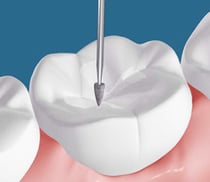

歯牙破折が歯冠部分で留まり、歯の神経まで達していない場合、歯の周りを一周削って型採りをしてからかぶせる方法を行います。

破折治療 クラウン